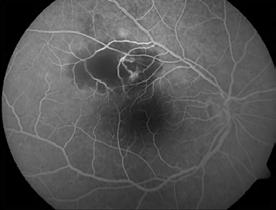

Type 3 MNV refers to the growth of vessels from the retinal circulation toward the outer retina. It is believed that vascular proliferation begins in the deep retinal capillary plexus, with the growth vector extending toward the outer retina. On FA and ICGA, Type 3 MNV appears as a hyperfluorescent intraretinal vascular complex with leakage in the late phases of the examination. Late-phase leakage ion ICGA is a unique feature of MNV lesions. Since these lesions originate from the retinal circulation, they never arise within the foveal avascular zone. Instead, they develop near its edge or at a variable distance from it, typically from the terminal portions of third-order arterioles and venules.5 (Figure 3)

Figure 3. Two examples of Type 3 macular neovascularization. In the first case, Indocyanine green angiography (B) and fluorescein angiography revealing the Type 3 macular neovascularization (arrowhead). Optical coherence tomography (C) showing the detachment of retinal pigment epithelium with the hyperreflective material related to the neovascularization. In the second case, optical coherence tomography (E) showing the intraretinal hyperreflective material related to the neovascularization with intraretinal fluid. Fundus autofluorescence (F) showing abnormalities of retinal pigment epithelium. Optical coherence tomography angiography (G) showing the neovascular lesion.